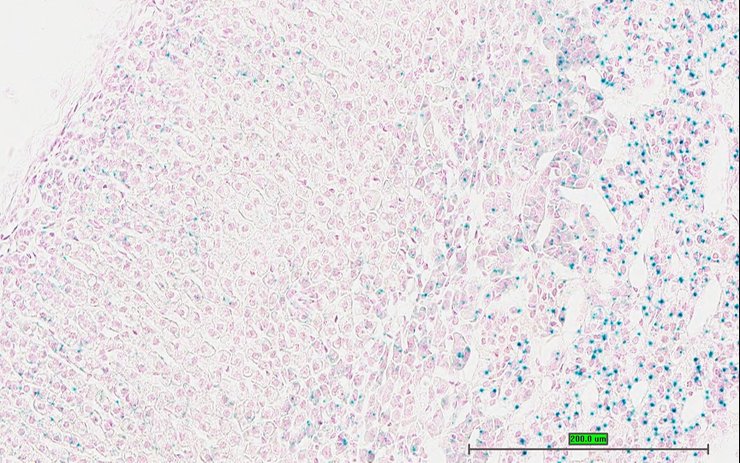

TS28: ovary Present UC Davis_1884113

Specimen UC Davis_1884114: postnatal adult; Sumo1tm1.1(KOMP)Vlcg/Sumo1+ (more )